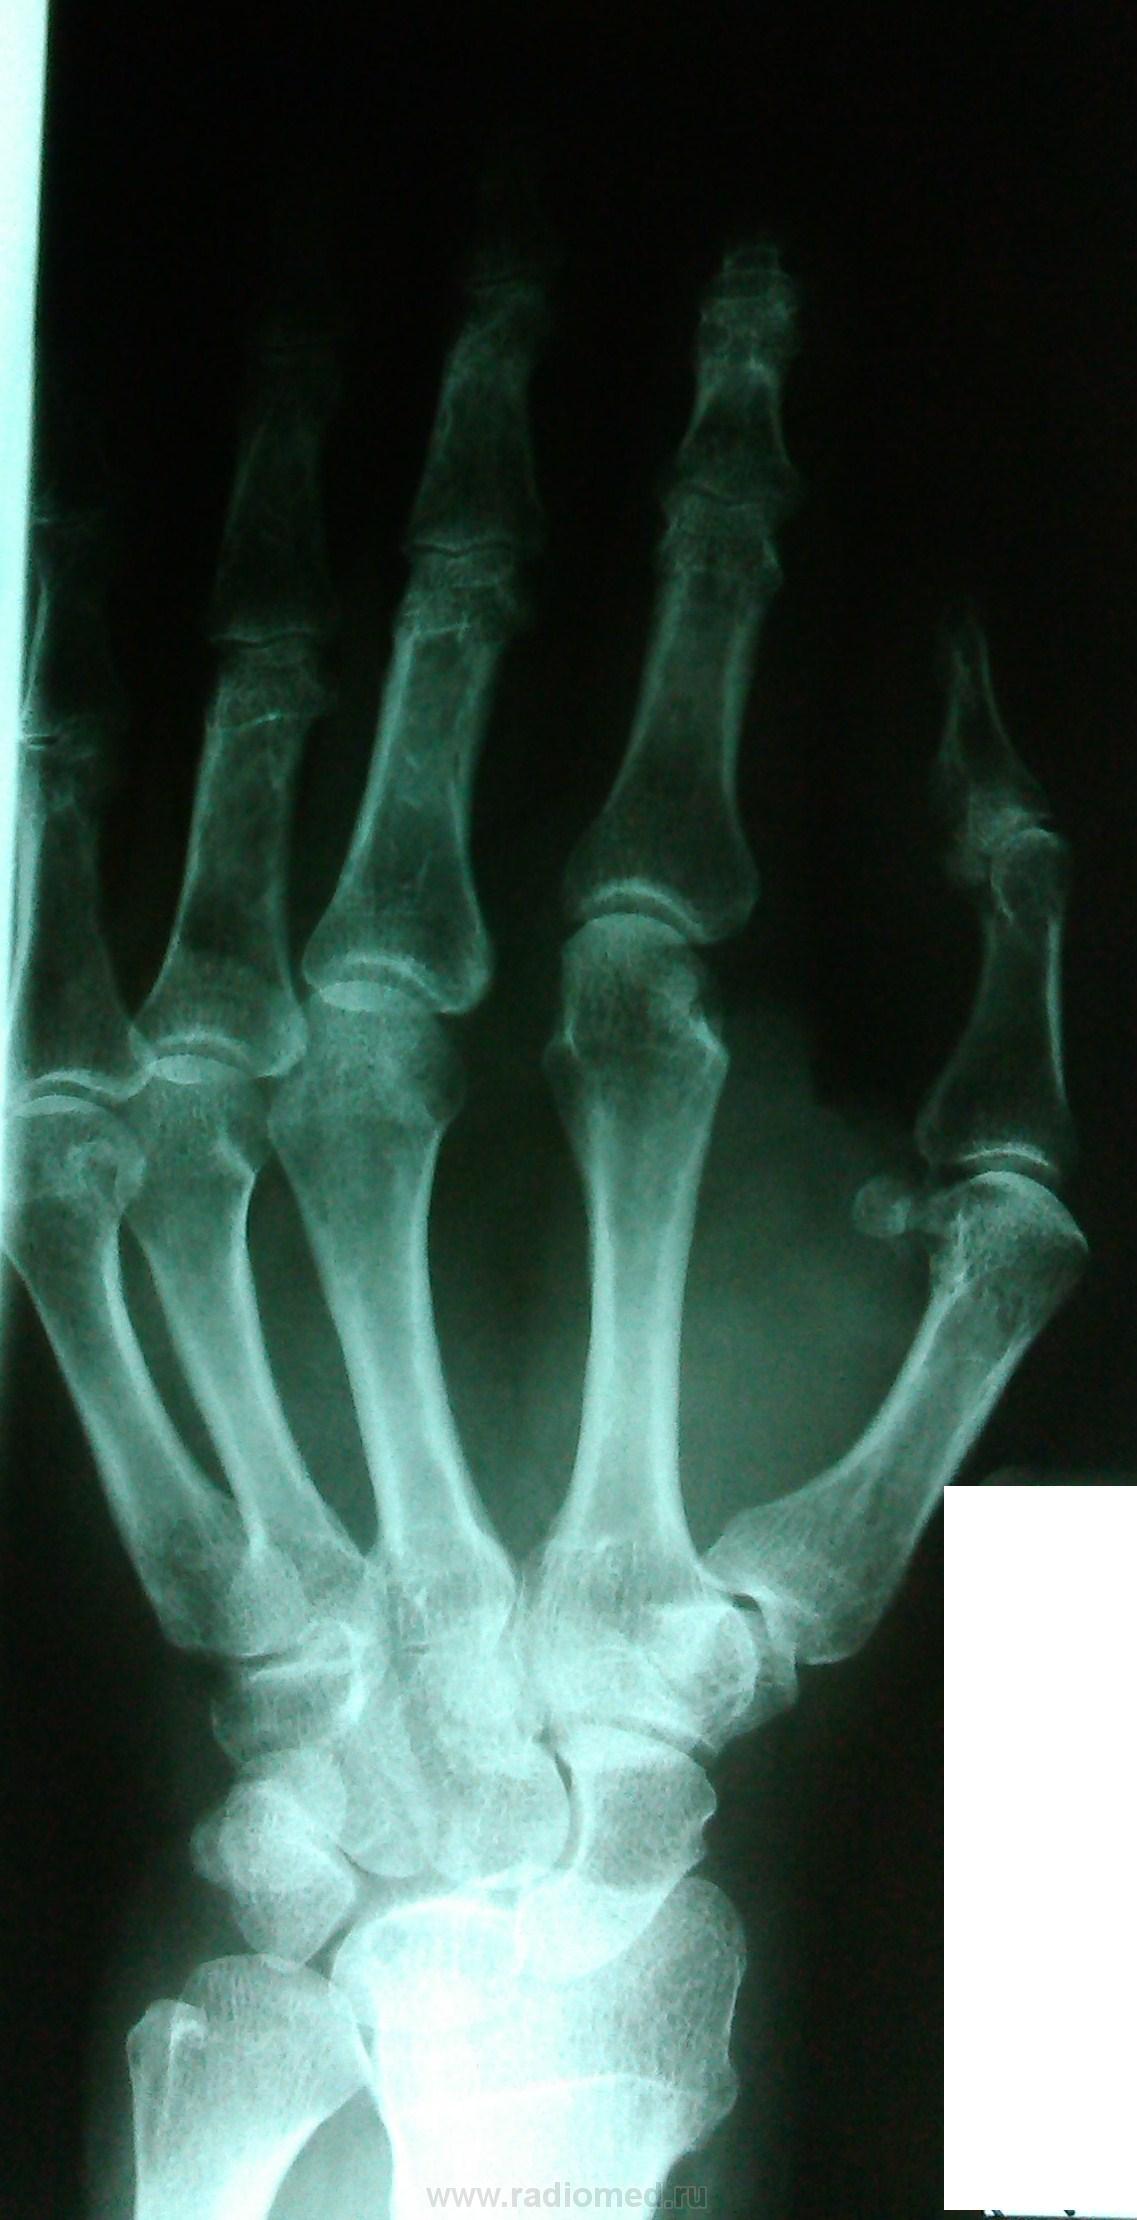

Пол пациента: Мужской пол Тип патологии: Другое Область исследования: Скелетно-мышечная система Методы исследования: Rg Пациент, 64 года. C диагнозом контрактура левой кисти. Как описывать в данном случае? https://radiomed.ru/sites/default/files/styles/case_slider_image/public/user/18609/img_20130822_121905.jpg?itok=m1BEXT25 ID:31041 Thu, 22/08/2013 - 21:46 #1 Катенёв Валенти... Offline Last seen: 7 years 2 months ago Joined: 22.03.2008 - 22:15 Posts: 54876 Что контрактура, "рентгенологический диагноз"? Fri, 23/08/2013 - 00:19 #2 Алексей Игореви... Offline Last seen: 6 years 11 months ago Joined: 08.08.2012 - 21:52 Posts: 786 Контрактура суто клинический диагноз, описывайте, скорее, как полиартрит суставов кисти. "Обучая других - учишься сам". Н.И.Пирогов Fri, 23/08/2013 - 17:40 #3 Катенёв Валенти... Offline Last seen: 7 years 2 months ago Joined: 22.03.2008 - 22:15 Posts: 54876 На мой взгляд, косячит Ваш лаборант с укладками, или что с трубкой?Приложения:

Контрактура суто клинический диагноз, описывайте, скорее, как полиартрит суставов кисти.